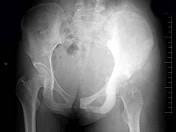

问题 女,16岁,左臀部疼痛伴发热2个月,摄片如图所示,最可能的诊断是?(?)

选项 A.左髂骨成骨肉瘤 B.左髂骨急性化脓性骨髓炎 C.左髂骨软骨肉瘤 D.左髂骨网状细胞肉瘤 E.以上均不正确

答案 A